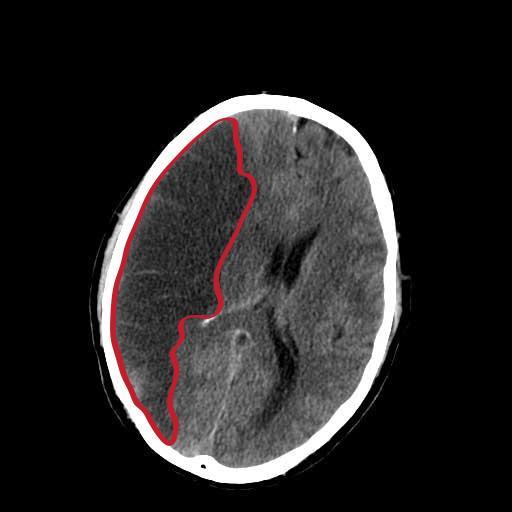

做核磁共振结果脑内多发缺血及梗塞灶

根据你的颅脑核磁描述,结果应该是缺血灶和腔梗。没有新发的急性期脑梗死。这个一般就是可以口服活血化瘀药物,平时多注意,控制血压,血脂,不要出现急...

脑内多发缺血灶严重吗?

大多数的情况下患病的患者是不严重的,这是脑动脉粥样硬化的一种表现,刚开始治疗的时候以控制血压、血脂或者用活血化瘀的药物为主,如果多次发生腔隙性脑梗塞,...

脑缺血灶,一般不会影响到人的寿命,因此不用担心其病情的严重程度。我们应该重视脑缺血灶后面所隐藏的一些重要信息,脑缺血灶是在头颅影像学中所用的...